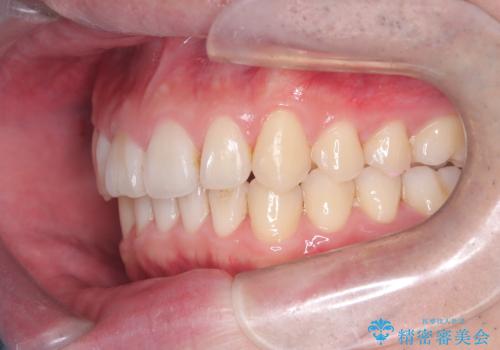

- 前歯が出ていることを主訴に来院されました。

歯列の幅が狭かったため、横に広げながらスペースを作り、叢生の改善を行いました。

左側の犬歯関係も治療前より良い状態で治療を完了することができました。

今回は臼歯部の遠心移動を行うために2級ゴムを使用しています。